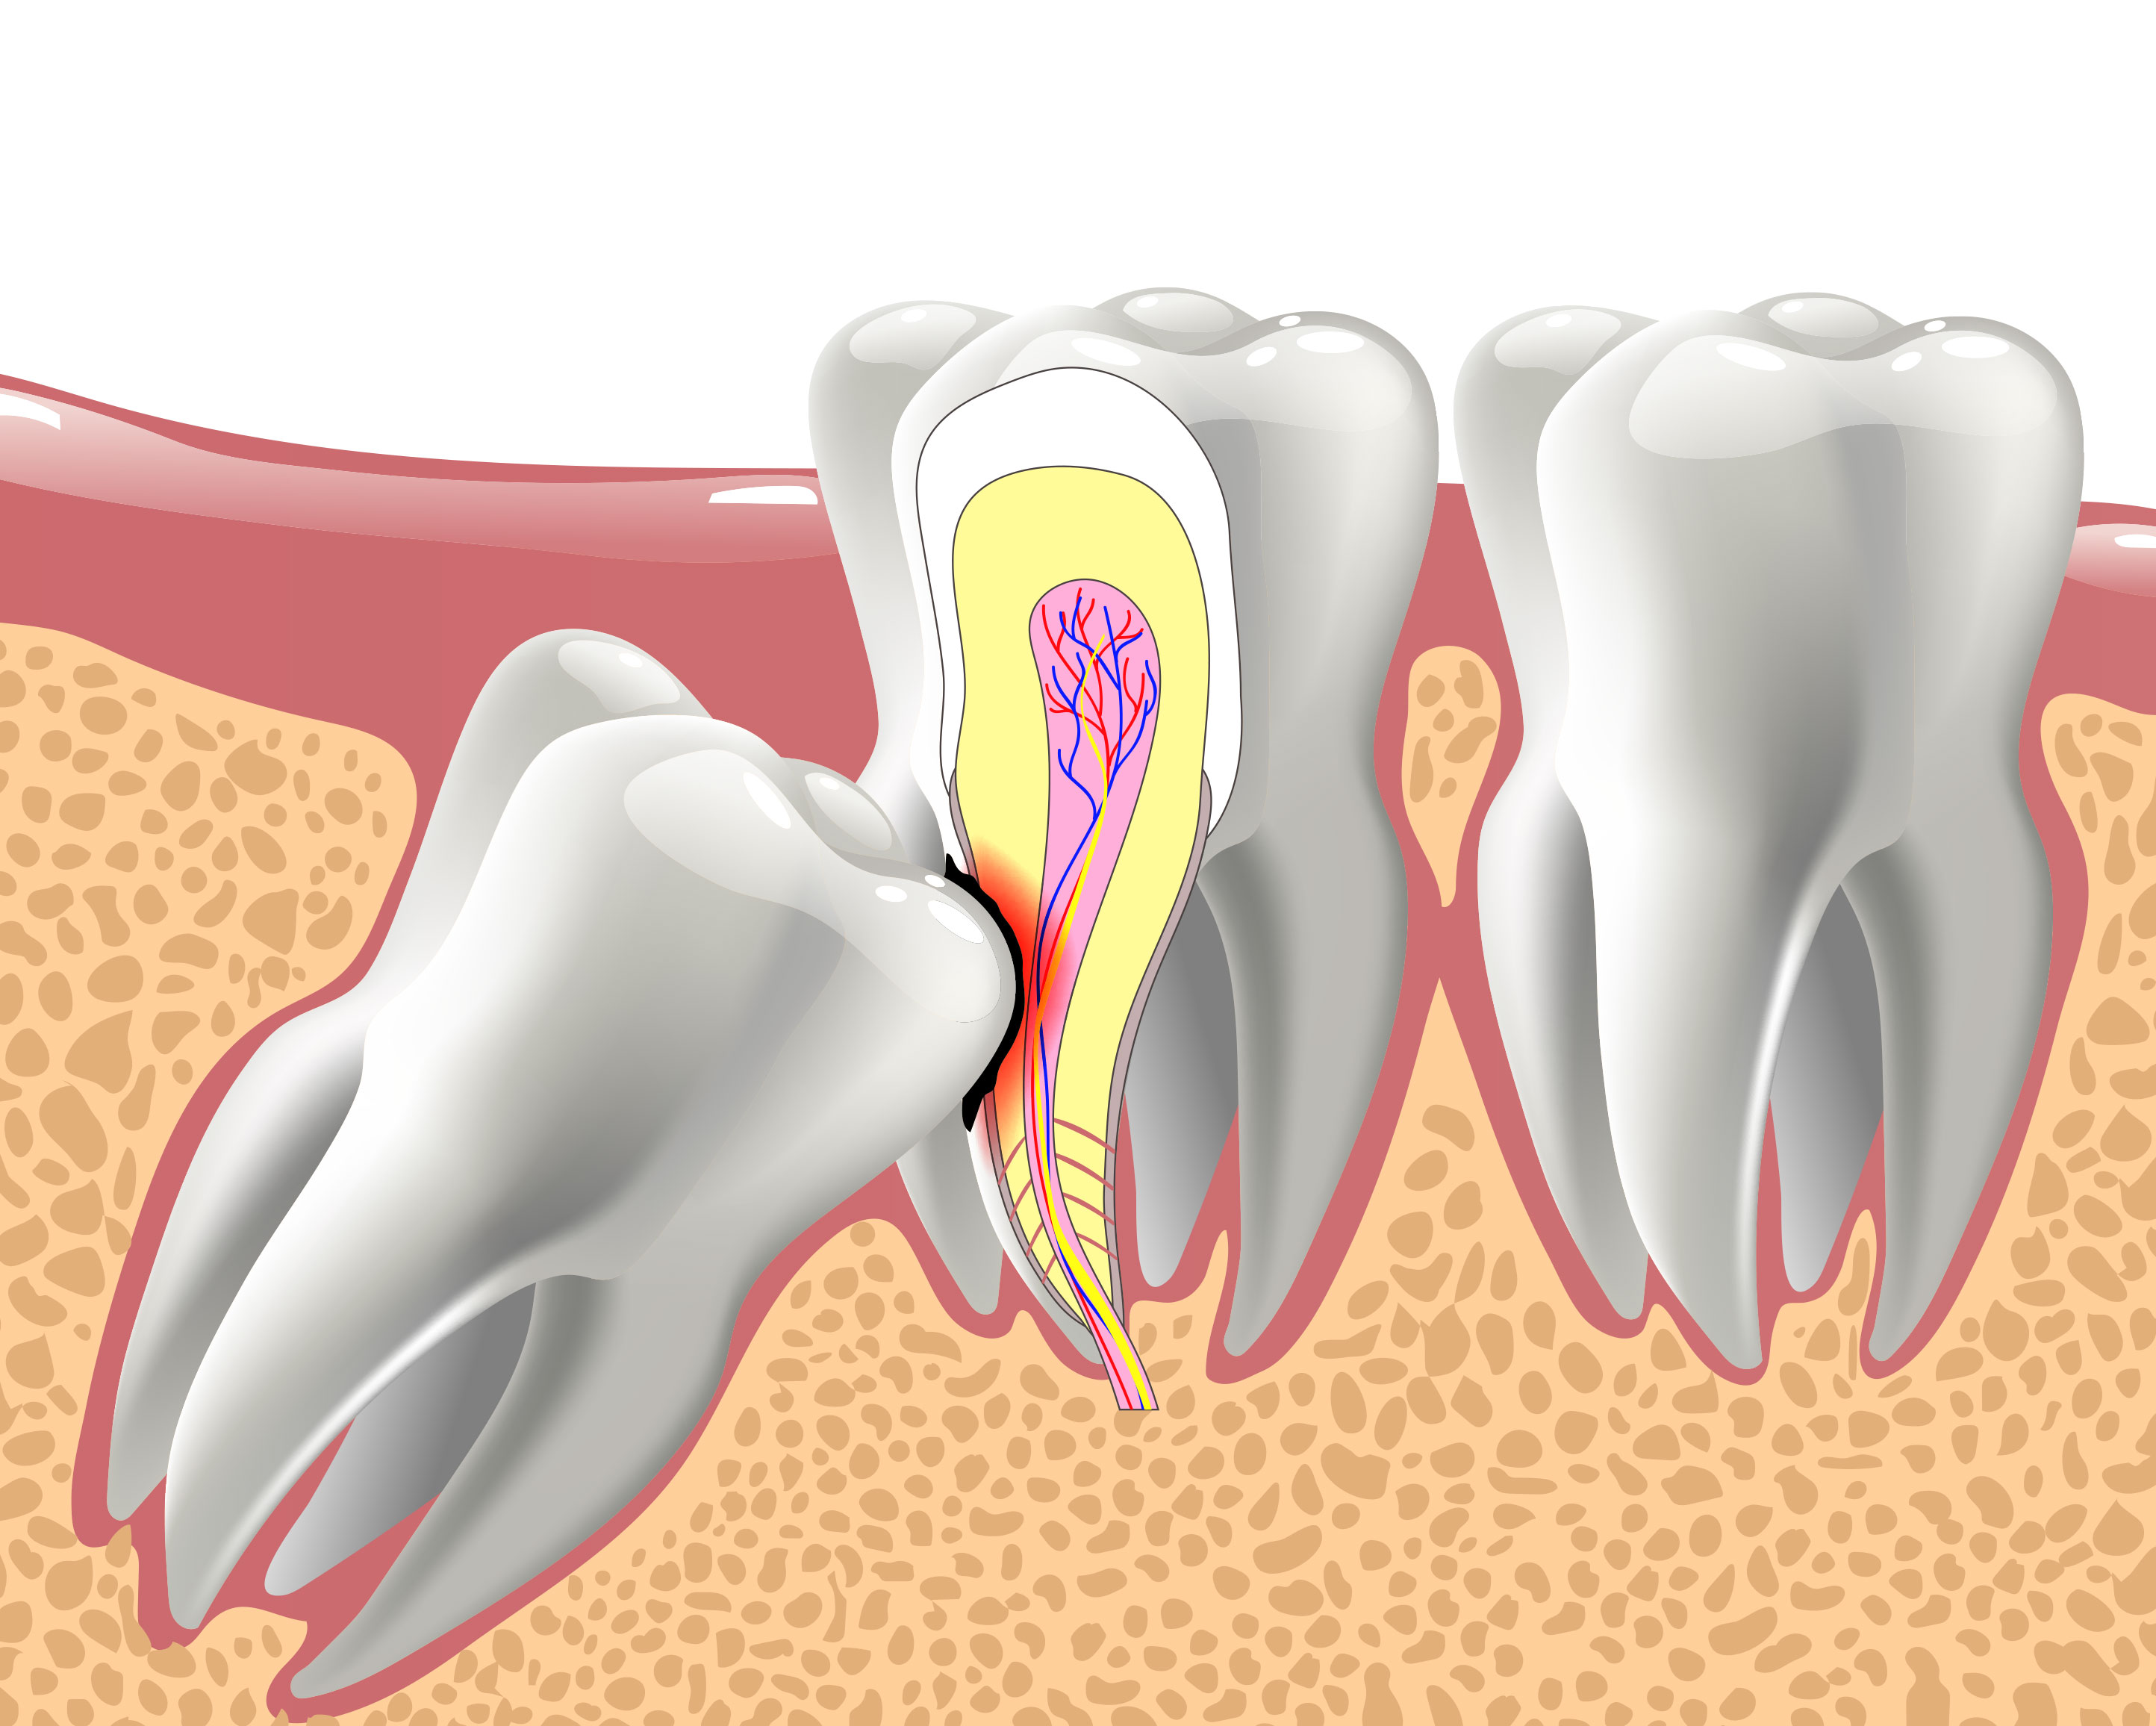

Miramar Beach Oral Surgery Services

Oral Surgeon in Miramar Beach